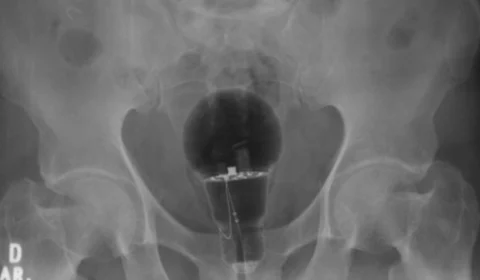

Homem põe lâmpada no ânus e vai parar no hospital com medo de avisar esposa

Paciente colombiano de 53 anos diz não saber como a lâmpada foi parar em seu ânus e tenta esconder o incidente de sua esposa.